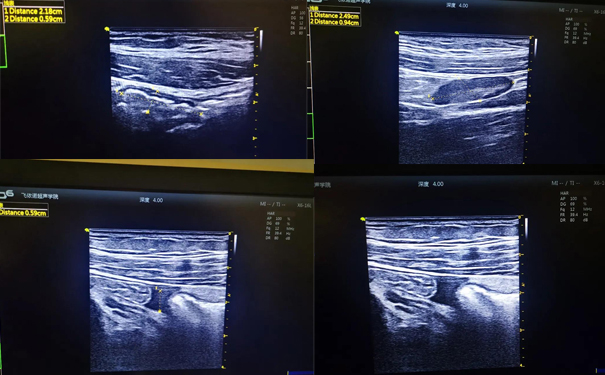

1间教室,1台便携超声,1名超声医生

飞依诺彩超设备扫查

飞依诺便携超声为当地老人进行心脏扫查

经过仔细的腹部便携超声检查

VINNO 6迅速地锁定了病因:阑尾炎